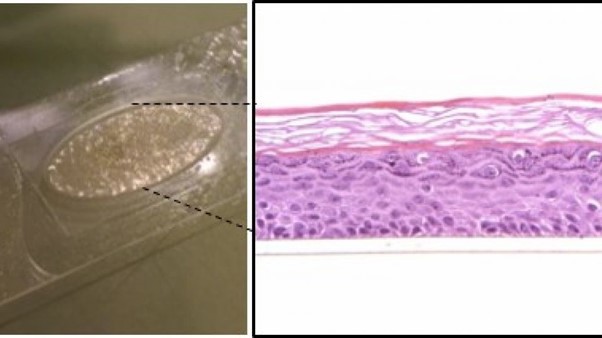

Organotypische menselijke huidequivalenten (HSE's) zijn in het lab gekweekte modellen die direct zijn ontwikkeld uit volwassen menselijke cellen die zijn geïsoleerd uit normale of zieke menselijke huid. Deze cellen worden daarna in ‘malletjes’ geörganiseerd op dezelfde manier die we ook in onze echte huid zien zodat ze de structuur goed nabootsen. We werken ook met zogeheten ‘huidorganoïden’, deze 3D structuren maken we met stamcellen die zichzelf organiseren tot huidmodellen met daarin verschillende celsoorten. Beide systemen lijken in hoge mate op de menselijke huid en worden gebruikt voor toxiciteitstests, maar ook om huidziekten te bestuderen, zoals wondgenezing, huidkanker, infecties en atopisch eczeem. Op deze manier dienen ze als uitstekende alternatieven voor dierproeven en dragen ze bij aan de ontwikkeling van nieuwe behandelingen.